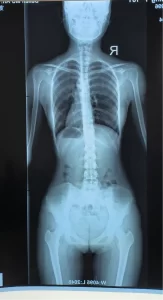

问题类型:脊柱S弯,矢状面生理曲度改变

影像学检查:生理曲度胸椎过度后凸,胸腰段右凸